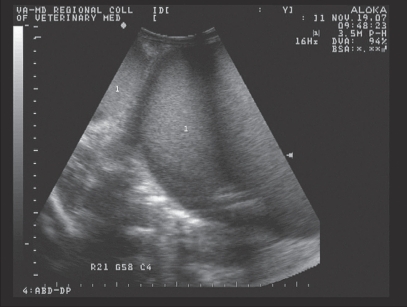

An 18-month-old llama was presented for reproductive evaluation. She had a history of being bred 3 times prior to examination, with the male apparently having difficulty positioning himself at each mating. This was described by the owners as the relatively more caudal position of the male over the female’s dorsum during intromission. As the mating attempt progressed, the female appeared to become progressively more uncomfortable and had a tendency to lie in lateral recumbency. Physical examination at presentation was unremarkable. Rectal examination revealed a fluid-filled viscus consistent with the uterus. Transabdominal and transrectal ultrasound (Figure 3) confirmed the presence of a fluid-filled (grade 1 out of 4) structure consistent in appearance with the uterus.

Figure 3.

Transrectal ultrasonographic appearance of fluid-filled uterus in the llama (case 2), with the bladder (1) and uterus (2) demonstrated. Each hatched line of the left of the image represents 1 cm.